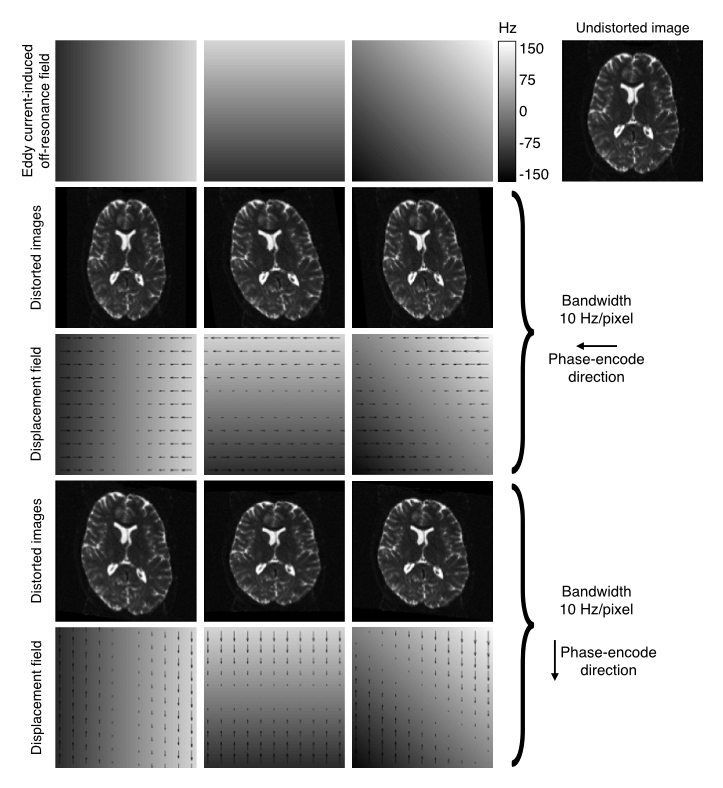

The seminal paper by Jezzard el al. describes the distortions as a \(yx\)-shear, a \(y\)-zoom and a \(z\)-translation. This was predicated on the EC-induced field being a linear combination of \(x\), \(y\) and \(z\) linear gradients, the PE-direction being along \(y\) and on considering it as a 2D problem. In the figure below is a more general explanantion for how the EC-induced fields translate into distortions.

| Explanation of how EC-fields translate into distortions. |

|---|

|

| The top row shows EC-fields linear in the $x$, $y$ and $xy$-directions in columns 1-3 respectively. The fourth column shows an undistorted image. Row two shows the resulting distorted images for data acquired with the phase-encoding in the $y$-direction, and row three shows the corresponding displacement fields. Rows four and five shows the same for the case where the phase-encoding is in the $y$-direction. |

The fields and distortions in the figure above still assume that the EC-fields are "perfect" linear combinations of linear gradients. However, that is not a given and there is ample evidence that this is not generally true (I would personally go as far as to say the it is generally not true). When validating eddy on the HCP data we found strong evidence both for quadratic and cubic terms, even though the cubic terms where sufficiently small to safely ignore even though they could be reliably detected.